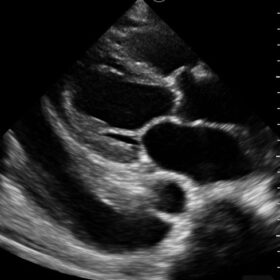

Mindray I3P WiFi Probe Image Gallery and Videos